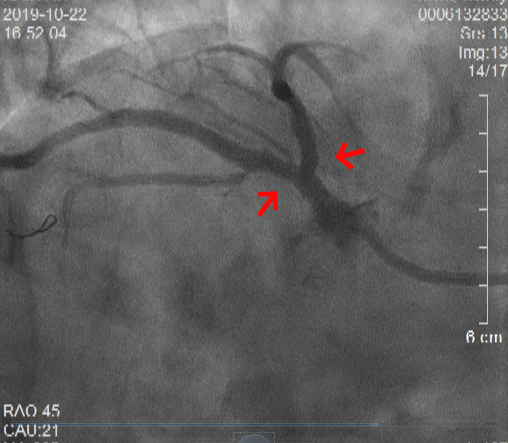

术前冠状动脉造影显示:镜像右位心、前降支和回旋支开口处严重病变

入院第二天,心内科柴大军主任医师为核心的介入团队为俞老先生进行了评估。此时俞老先生已可平卧,柴大军主任医师当机立断为其行经皮冠状动脉介入治疗(PCI)。冠状动脉造影显示,俞老先生是极其罕见的右位心合并疑难的左主干分叉病变。